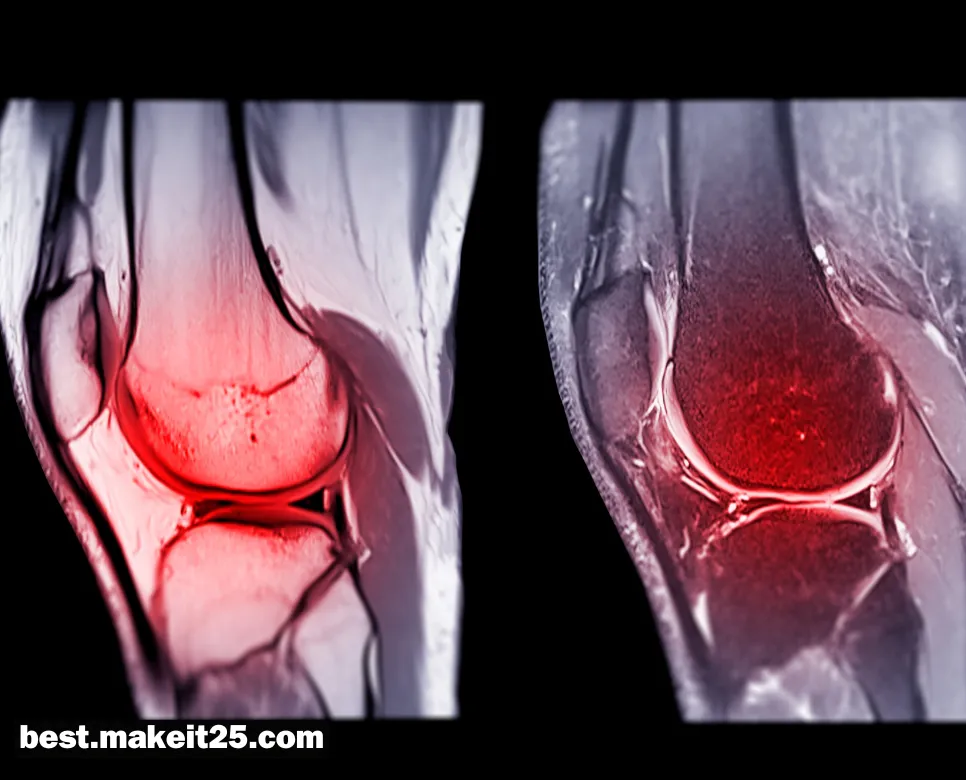

- 영상 검사: X-ray를 통해 골절 여부를 확인하고, MRI를 시행하여 ACL 손상을 확진합니다.

ACL은 “Anterior Cruciate Ligament”의 약자로, 한국어로는 “전방십자인대”를 의미합니다. 전방십자인대는 무릎 관절의 안정성을 유지하는 데 중요한 역할을 하는 인대로, 대퇴골과 경골을 연결합니다. 이 인대는 무릎의 전방 전위(앞쪽으로 밀리는 것)와 과도한 회전을 제한하여 관절의 안정성을 제공합니다. ACL 손상은 스포츠 활동 중 급격한 방향 전환이나 착지 시 흔히 발생하며, 무릎의 불안정성, 통증, 부종 등을 야기할 수 있습니

ACL 손상의 진단